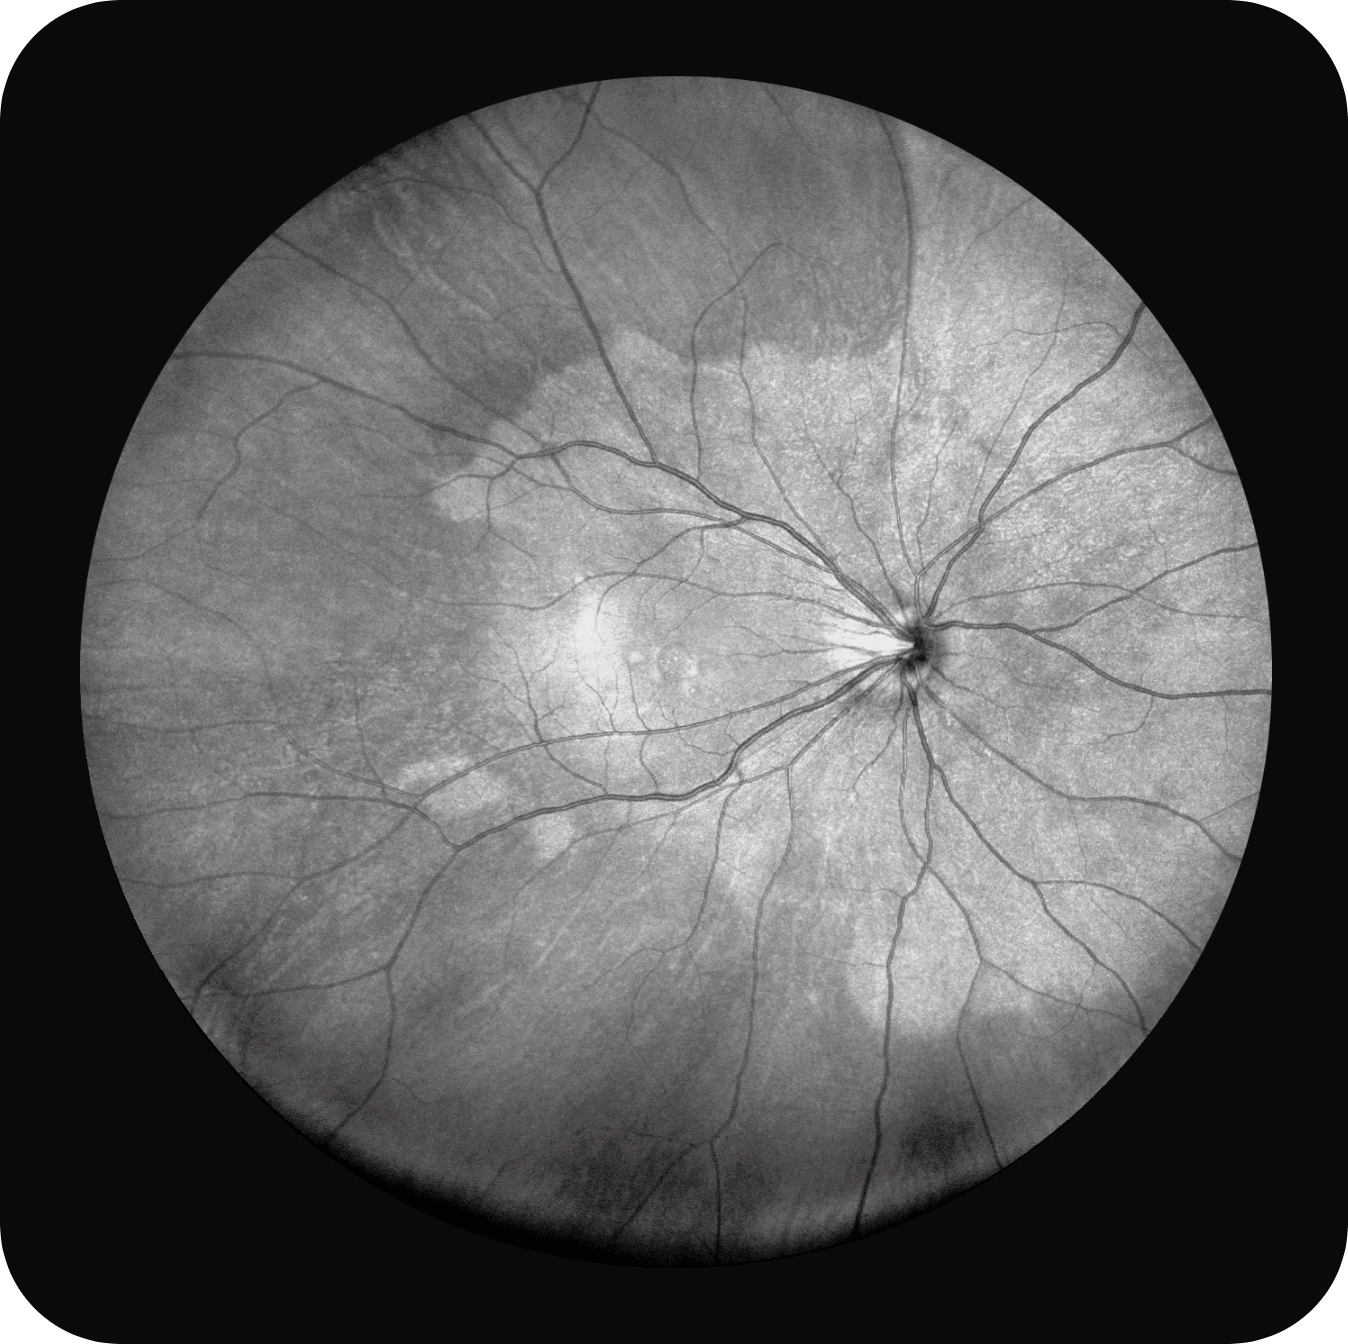

Uma única varredura pode obter rapidamente imagens sincronizadas de imagens coloridas de campo ultralargo/FAF/FFA/ICGA e SS-OCT, alcançando sincronização em tempo real e alinhamento preciso de imagens planas e estruturais da retina, melhorando significativamente a eficiência da inspeção e otimizando o processo de diagnóstico e tratamento.” Uma única varredura pode obter rapidamente imagens sincronizadas de imagens coloridas de campo ultralargo/FAF/FFA/ICGA e SS-OCT, alcançando sincronização em tempo real e alinhamento preciso de imagens planas e estruturais da retina, melhorando significativamente a eficiência da inspeção e otimizando o processo de diagnóstico e tratamento.

Multi-Modalidade

Altamente integrado com tecnologias como SLO confocal e SS-OCT, ele combina imagens coloridas SLO de campo ultralargo, angiografia confocal a laser, autofluorescência e imagens tomográficas de segmento anterior e posterior ultraamplas e profundas em um único sistema.

OCTA até 220° em mosaico, para análise detalhada da vascularização.